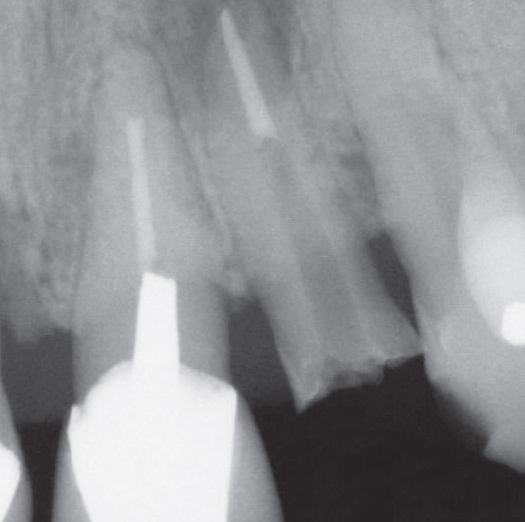

After

After Root Canal treatment